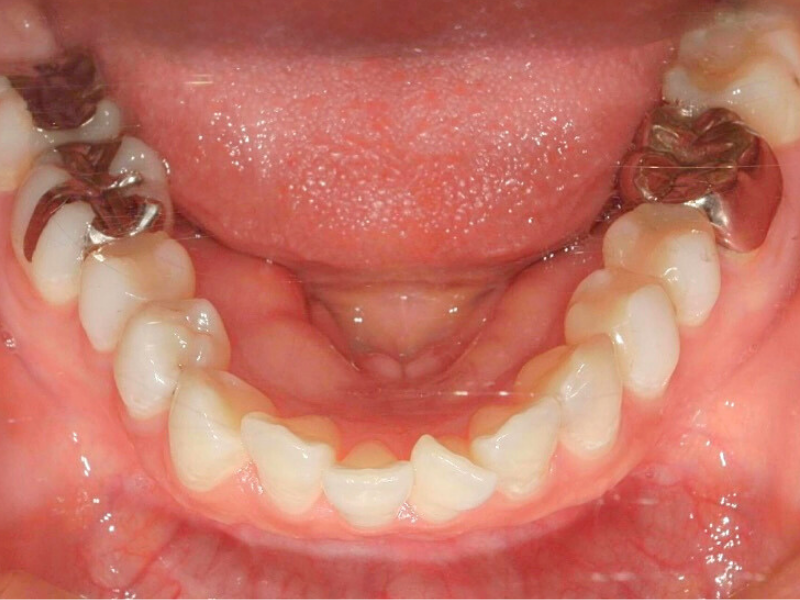

20代、男性、ワイヤー

| 施術内容 | 主訴:でこぼこで食べ物がよく挟まる。虫歯や歯肉炎に悩まされてきた。 詳細:ワイヤー矯正での歯並び改善 とても磨きやすくなったと満足されてます。 |

|---|---|

| 治療期間 | 16ヶ月(2/3現在 治療終了) |

| リスク・副作用 | ■リスク・副作用 ・治療の初期段階では、痛みや不快感が生じやすくなりますが、一週間前後で慣れます。 ・歯の動き方には個人差があるため、予想された治療期間より延長する場合があります。 |

| 費用 | ワイヤー矯正 60万円(税込660,000円) |